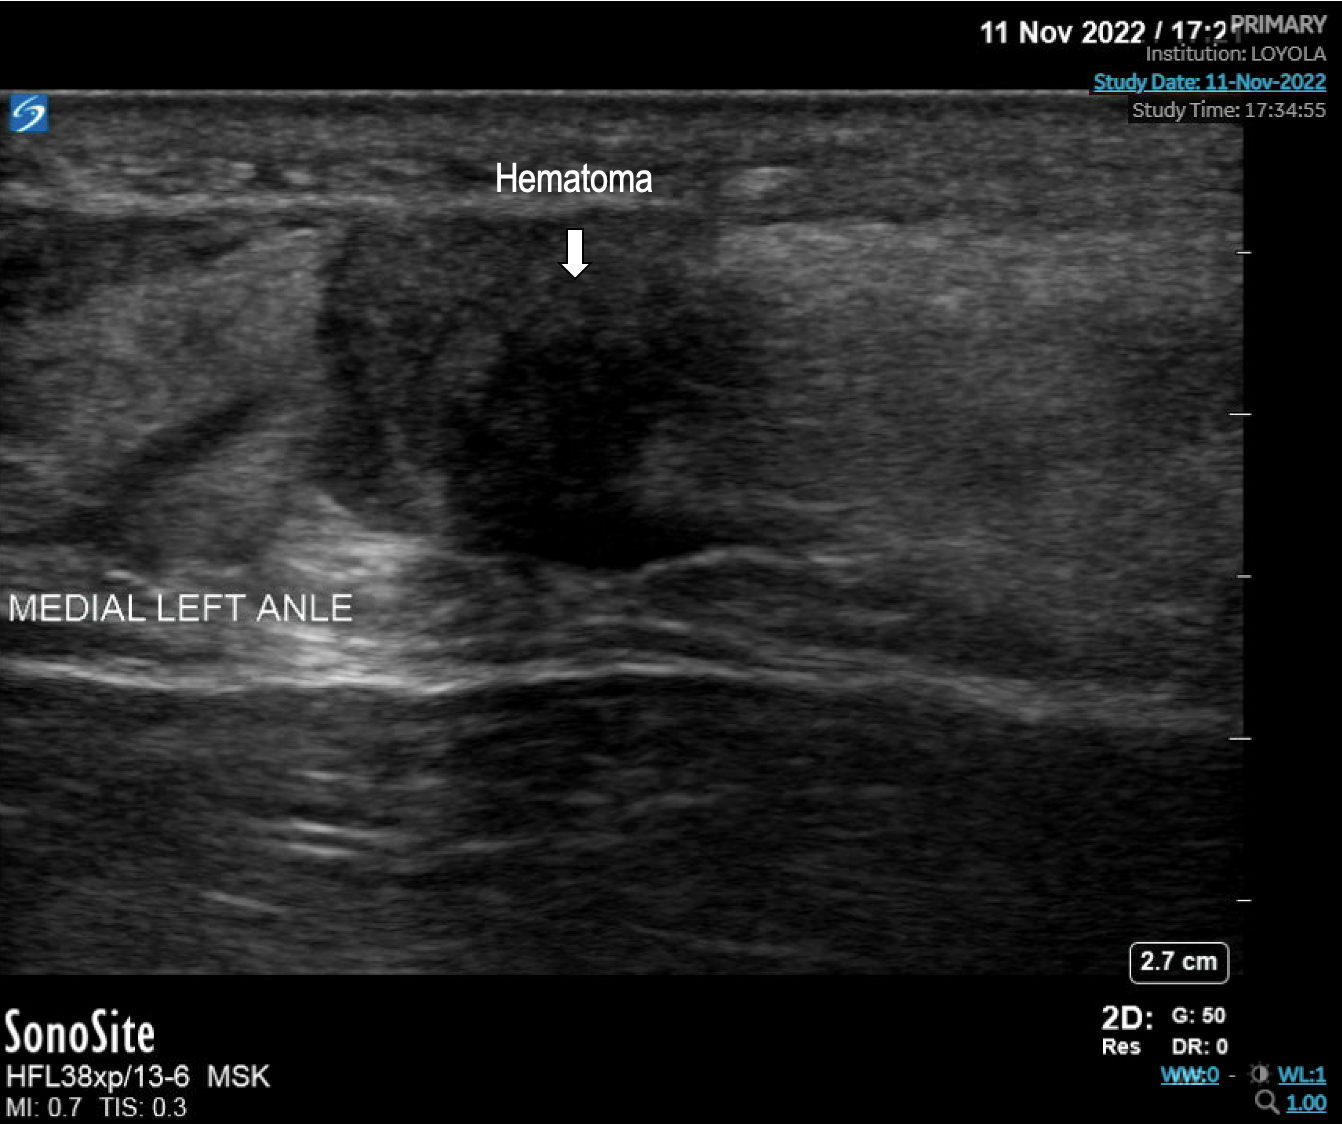

The linear probe is in the longitudinal position. The distal Achilles is on the right, proximal on the left, and the hematoma caused by the rupture is visualized in the center of the image.